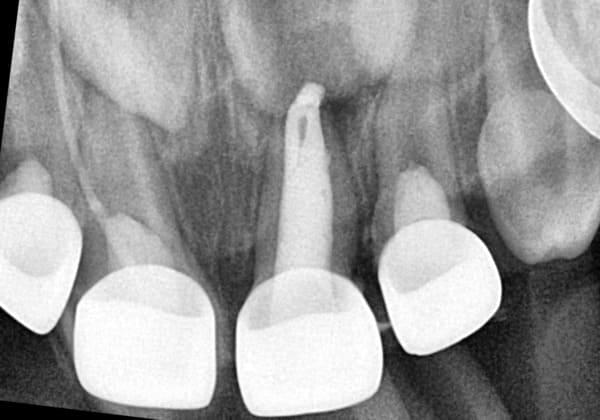

Система кореневих каналів молочних зубів часто складніша, ніж у постійних. Тому ми використовуємо ізоляцію робочого поля за допомогою кофердаму та спеціальне обладнання, щоб гарантувати високу якість лікування.

Важливо розуміти: це не швидка процедура. Вона вимагає ретельного очищення, промивання та пломбування каналів спеціальними матеріалами. Поспіх у цій справі може призвести до серйозних ускладнень у майбутньому.